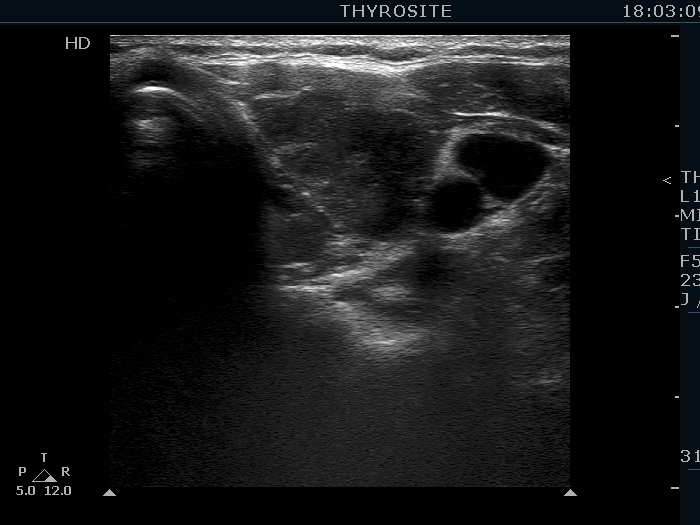

Second examination 19 months later (second row of images):

Comment. This is a typical presentation of a newly developed hypothyroidism regarding the change in echo pattern. Although the correlation between the echogenicity index and the hormonal status is week, in a particular patient, a developing hypothyroidism from an euthyroid state usually correlates with an increasing echogenicity index.Clinical data: This time the patient had no complaints, however the TSH was 16.8 mIU/L two month ago.

Palpation: no abnormality.

Laboratory tests: TSH 29.1 mIU/L, FT4 13.1 pM/L, aTPO 638 U/mL.

Ultrasonography. Compared with The previous examination, one change could be observed: the echogenicity index rose to 70-90%.

Daily 75 microgram levothyroxine was administered.